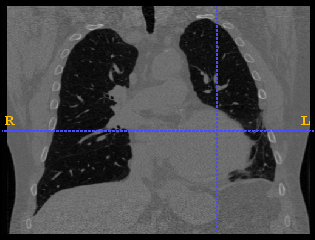

This paper presents a modelling approach that produces Anatomically Valid Airway tree conformations (AVATREE). Such conformations are adapted to personalized geometry and boundary conditions derived from diagnostic imaging and well-established airway extraction methods. Specifically, this study aims to provide an open-source simulation framework to (i) exploit imaging data so as to provide patient-specific representations (ii) perform structural analysis (iii) extend the segmented airway tree to predict the airway branching across the whole lung volume (iv) visualize probabilistic confidence maps of generation data (v) simulate bronchoconstriction to (vi) access patient-specific airway functionality (vii) perform fluid dynamics simulation in patient-specific boundary conditions to access pulmonary function.